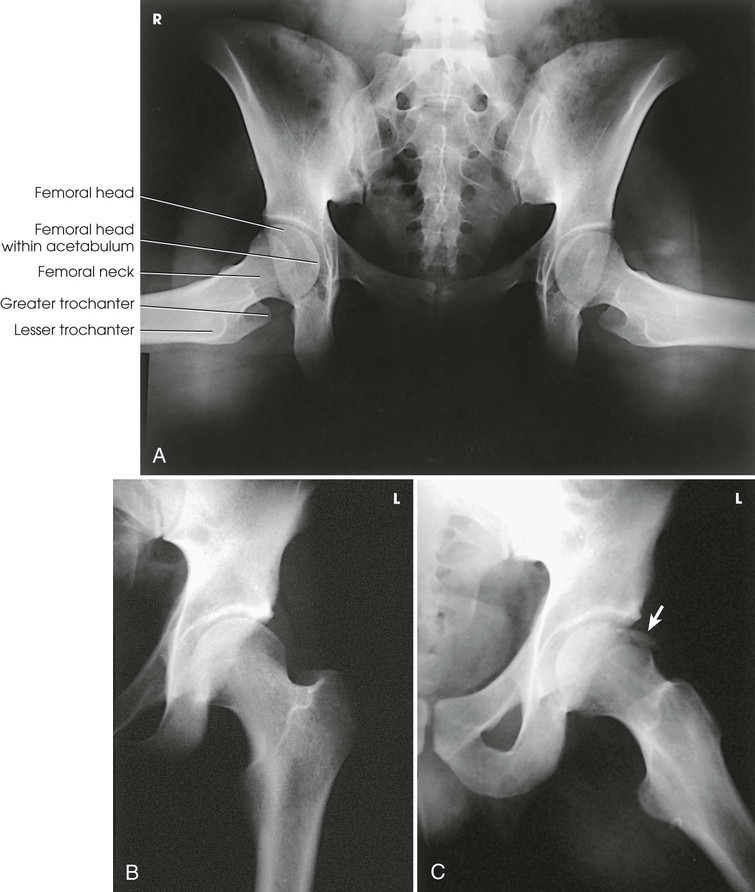

The femur is the longest, strongest, and heaviest bone in the body. The proximal end of the femur consists of a head, a neck, and two large processes—the greater and lesser trochanters (Fig. 7-4). The smooth, rounded head is connected to the femoral body by a pyramid-shaped neck and is received into the acetabular cavity of the hip bone. A small depression at the center of the head, the fovea capitis, attaches to the ligamentum capitis femoris (Fig. 7-5; see Fig. 7-4). The neck is constricted near the head but expands to a broad base at the body of the bone. The neck projects medially, superiorly, and anteriorly from the body. The trochanters are situated at the junction of the body and the base of the neck. The greater trochanter is at the superolateral part of the femoral body, and the lesser trochanter is at the posteromedial part. The prominent ridge extending between the trochanters at the base of the neck on the posterior surface of the body is called the intertrochanteric crest. The less prominent ridge connecting the trochanters anteriorly is called the intertrochanteric line. The femoral neck and the intertrochanteric crest are two common sites of fractures in elderly adults. The superior portion of the greater trochanter projects above the neck and curves slightly posteriorly and medially.

Structures shown

The resulting image shows the head, neck, trochanters, and proximal one third of the body of the femur (Fig. 7-31). In the initial examination of a hip lesion, whether traumatic or pathologic in origin, the AP projection is often obtained using an IR large enough to include the entire pelvic girdle and upper femora. Progress studies may be restricted to the affected side.

The resulting image shows a lateral projection of the hip, including the acetabulum, the proximal end of the femur, and the relationship of the femoral head to the acetabulum (see Figs. 7-33 and 7-34).